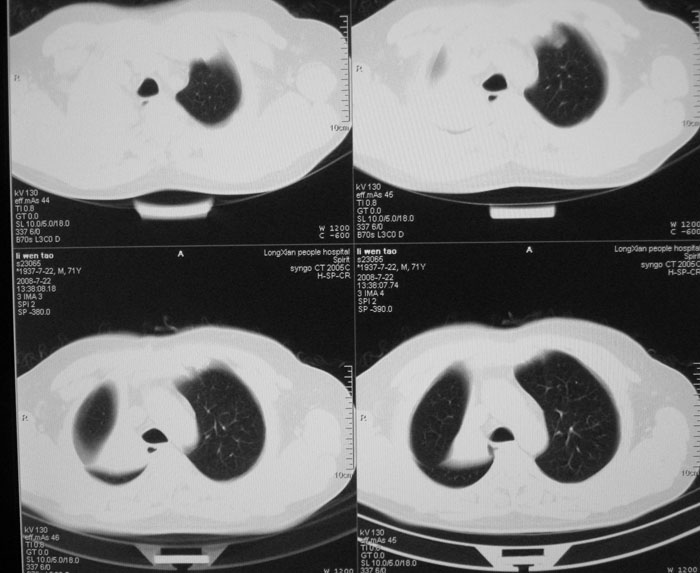

以下是引用wwwwtyy在2008-7-27 17:46:00的发言:[br]中心型肺癌不除外

以下是引用子十在2008-7-27 17:49:00的发言:[br]考虑中心性肺癌

以下是引用晓杰在2008-7-27 19:20:00的发言:[br]支持楼主意见;中心型肺癌不除外。